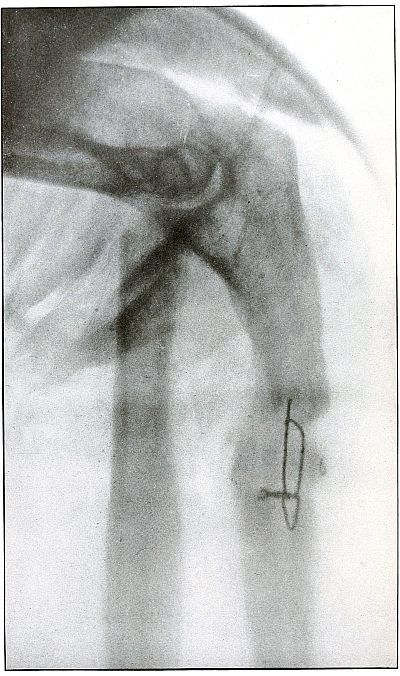

Plate 41.

_

Rifle—Plate 41.

UPPER EXTREMITY.

Gunshot Fracture of the Wrist.

Wound of entrance, posterior aspect of forearm over the lower end of the radius, with the bullet ranging forward and slightly downward to the wound of exit and covering with great laceration the anterior aspect of the wrist joint.

The range was close, and the energy of the high velocity of the missile was imparted to fragments, which, becoming “secondary missiles,” emerged with the projectile to cause extensive laceration and destruction of tissue.

The case was received for amputation in the second week, when a grave degree of infection extended in a cellulitis to the elbow. The ulnar nerve and vessels were intact, but the flexor tendons were almost entirely destroyed.

The plate, made after several weeks, when infection was under control and after the end of the radius and fragments of the carpus had been informally removed, shows a rarefaction of the carpus and proximal ends of the metacarpus, due to infection and disuse.

Frequent incisions and extension of drainage, with removal of detached fragments, was continued for several months. The wound was closed in the sixth month, with ankylosis and deformity of the wrist, as shown in plate 42. [Pg 94]